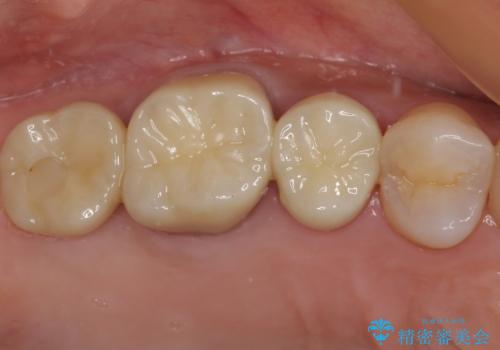

不安定な咬み合わせとなっており、クラウンの表面が剥離していたため、インプラントによる欠損補綴治療を行い、手前2つの歯も一緒に補綴治療を行うこととしました。

治療中の仮歯も頻繁に壊れておりましたが、インプラントの土台が歯肉上に出てからは咬み合わせが安定し、仮歯が壊れることもなくなりました。